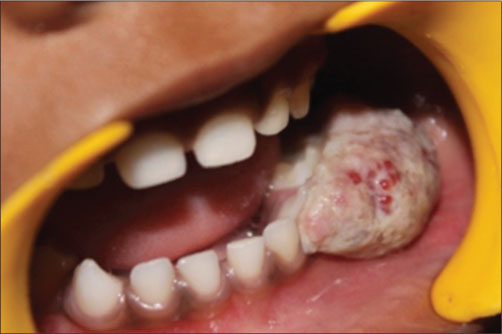

A 4-year-old female patient came with a complaint of growth in the lower back tooth region of lower jaw for 1 week. Parents of the patient noticed the growth a week back which was smaller in size initially which increased suddenly to the present size. Growth was not associated with pain or any other symptoms initially but later developed discomfort while eating associated with mild pain. The patient was given anti-inflammatory medication for the relief of pain and swelling for about 3 days, but there was no reduction in size of the growth. Medical and family histories were noncontributory. On extraoral examination, fullness is seen on the left lower third of face. A solitary left submandibular lymph node enlargement is felt, which is freely movable and tender. Intraorally, an exophytic growth was seen arising from gingiva in relation to 73, 74, and 75 tooth region [Figure 1] measured approximately around size 2 cm × 3 cm, slight pale in color with pinpoint erythematous areas. This appeared to be covered by keratotic surface and seemed to have papillary projections. On palpation, the lesion was pedunculated fibrous inconsistency, nontender, and slight bleeding on provocation, and diascopy test was negative. Considering the patient’s history and clinical examination, a provisional differential diagnosis was arrived which is as follows PG, verrucous hyperplasia, hemangioma, peripheral giant-cell granuloma, peripheral ossifying fibroma, fibroma, and peripheral odontogenic fibroma. The following sets of radiographs were advised to rule out any bony involvement. Intraoral periapical radiograph (IOPA) and occlusal radiographs showed soft-tissue shadow with respect to 73, 74, and 75 [Figure 2] and [3]. Later, complete blood picture was done which did not show any variations from the normal limits. The lesion was subjected for excisional biopsy under local anesthesia [Figure 4] and [5] and subjected to histopathological examination which revealed to be angiomatous granuloma [Figure 6] and [7]. The patient was followed up for 1 year after surgery and there was no evidence of recurrence.

| Figure. 1 Exophytic growth was seen arising from gingiva in relation to 73, 74, and 75 tooth region